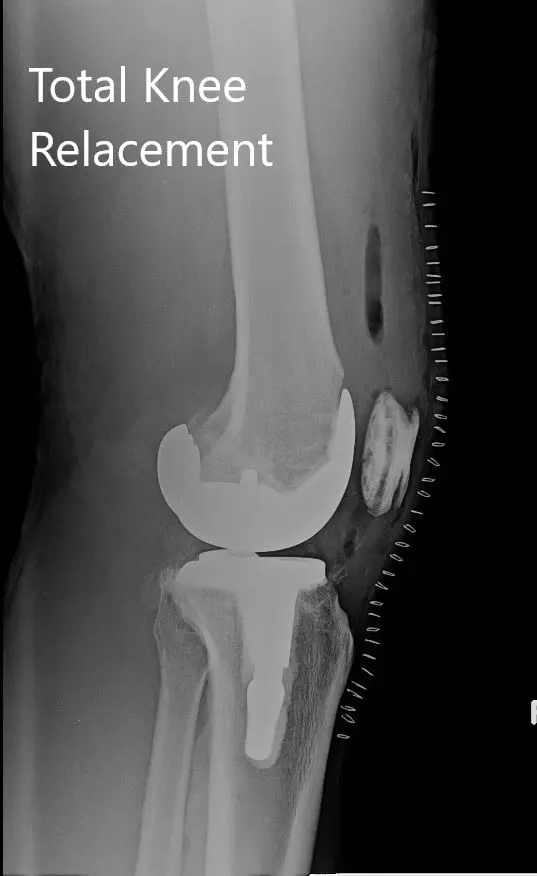

Postoperative X-ray of the right knee with a prosthesis in anteroposterior and lateral views.